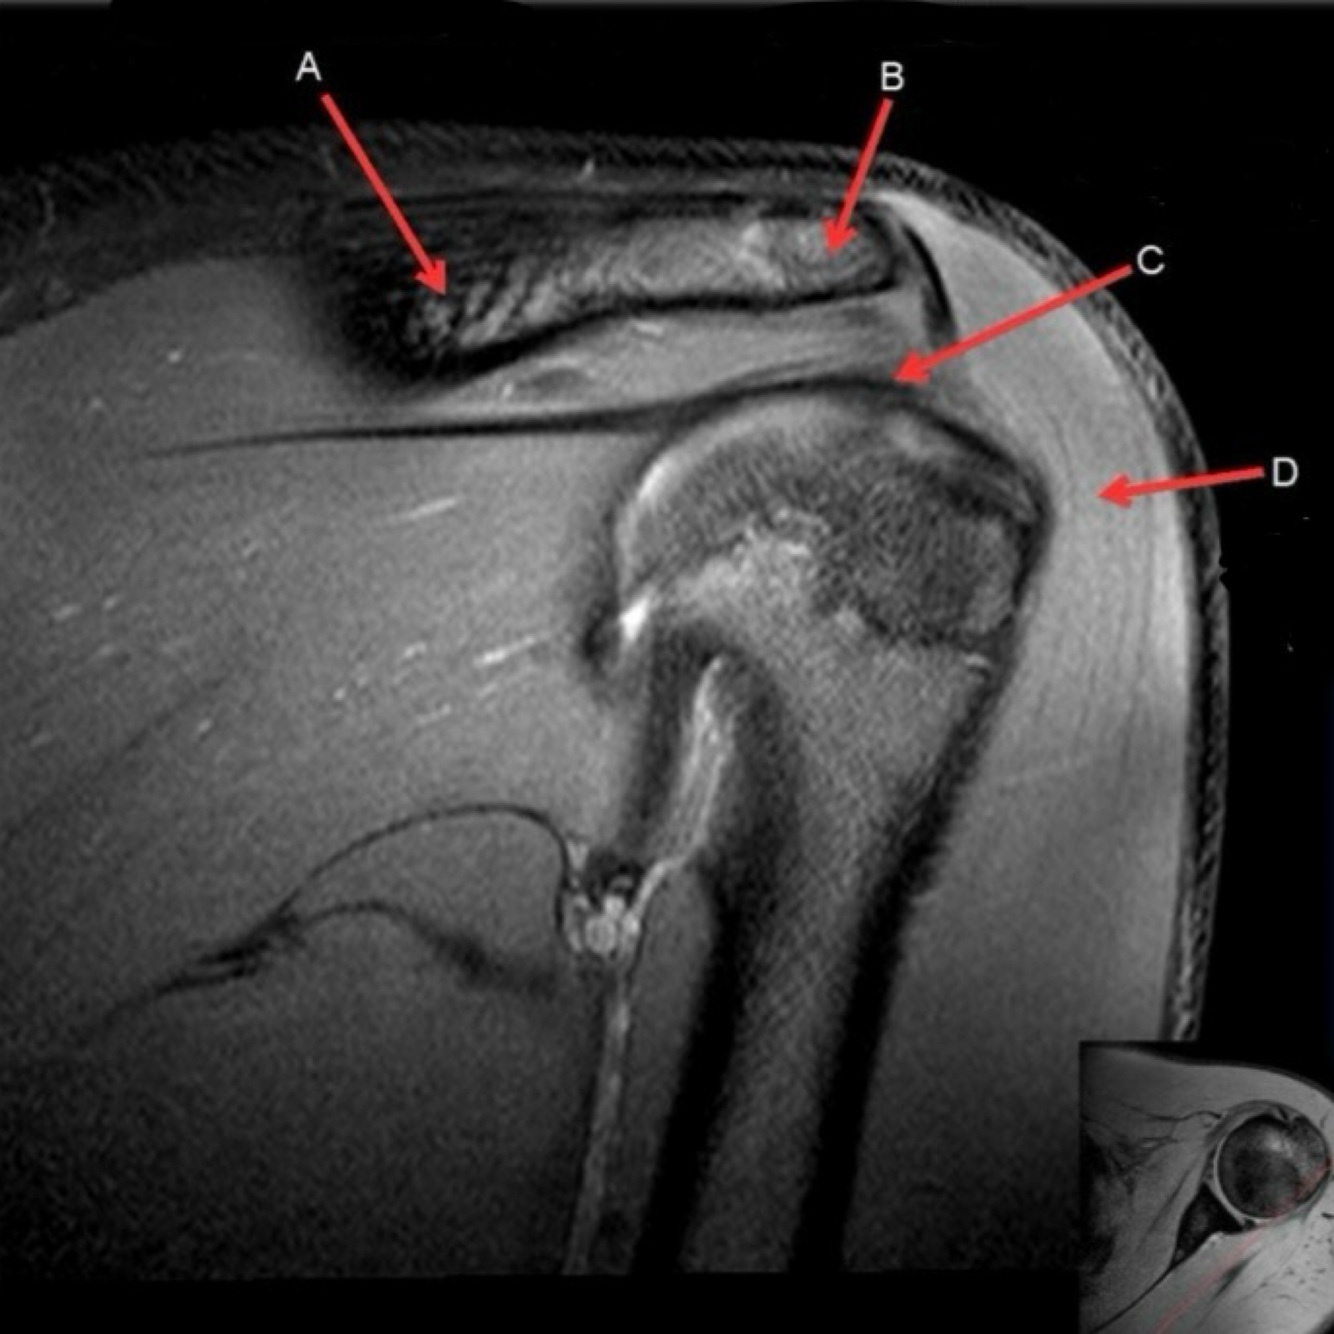

What is letter A?

ANTERIOR LABRUM

What is letter B?

BICEPS TENDON (LONG HEAD)

What is letter C?

HEAD OF HUMERUS

What is letter D?

POSTERIOR LABRUM